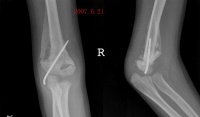

x线特征:受伤后不久可出现局限性肿快。伤后3-4周,在肿快内显示毛状致密象,其临近骨将显示骨膜反应。伤后6-8周,病变边缘部清楚地被致密骨质所包绕,而具有新生骨的外貌。软组织肿块的核心部有时显囊性变且逐渐扩大其内腔,到晚期而显出类似蛋壳状的囊肿。伤后5-6个月肿块收缩,因而肿块与邻近的骨皮质和骨膜反应之间显出x线透亮带。

局部软组织出现肿块,有时发热,伴有疼痛,关节活动受限。X线摄片示软组织内有不规则棉絮状模糊或关节周围云雾状的钙化阴影,以肘关节骨化性肌炎为例,在前臂伸屈肌、肱二头肌及肱三头肌近肘关节处采用轻柔适中的抚、摸、揉、推、弹、拨等手法。以松解剥离肌腱、腱膜及肌肉的粘连,其后术者一手持患肢腕部,一手持肘关节上中部,轻微持续牵引。再持患肢腕部轻柔地做肘关节无痛下的内收,外展和前后屈伸方向的抖动及环转手法,切忌手法粗暴及对局部肿块和关节囊行按摩刺激。

发热,局部皮温高,压痛,质硬肿块。局部肿块因逐渐骨化较前增大明显,肌肉僵硬萎缩,关节疼痛不明显,关节功能活动障碍。X线摄片示肿物周围花边状新骨大量生成,界限清楚,经过一段时间后,肿物停止发展并有所缩小,而形成较为致密的骨化性团块,可给予患肢依照早期手法按摩,然后术者一手持患肢肘关节近端,一手持患肢前臂中部。柔和稍用力逐渐被动屈伸肘关节,常常可听到骨化性肌炎断裂声,及粘连撕裂声此时肘关节的被动活动可达到基本正常范围。如遇骨性阻挡,切忌强行被动屈伸,以免再次发生骨折,应待骨化组织逐渐成熟及局限后。行手术治疗。手法治疗后,局部薰洗治疗,并指导病人在疼痛可耐受情况下,行肘关节以主动活动为主,被动活动为辅的功能锻炼。

局部无疼痛,肌肉僵硬萎缩严重,关节强直在某一体位或仅有轻微的活动度,X线摄片示出现壳状骨性软骨骨化,范围局限骨化明显致密,行手术切除骨化组织及关节松解术,用肘外侧切口在肱骨外髁嵴部,分别向肘前及肘后剥离,显露骨化组织后将其切除并彻底松解粘连组织,闭合切口前应松止血带,仔细止血放置负压引流术后经3周制动进行关节主动活动,以免再发生粘连待刀口愈合拆线后行中药熏洗治疗。